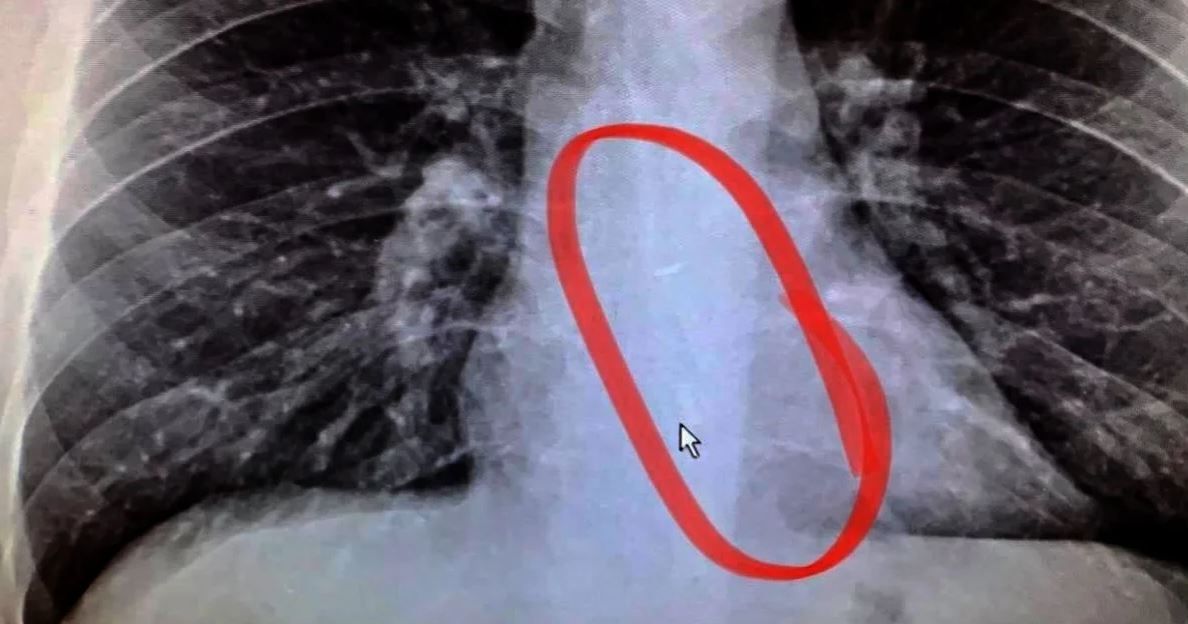

“Toda mi familia estaba boquiabierta, mirando la radiografía, en la pantalla donde se podía ver con una definición tan clara. Afortunadamente, me llevaron directamente a un centro de endoscopia”, agregó.